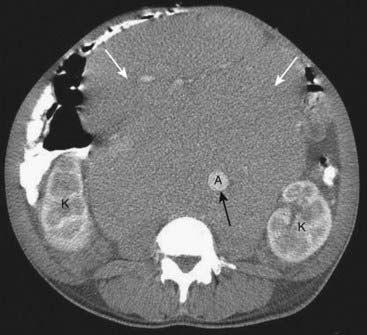

image

Figure 18-11 Free air from bowel perforation.

With the patient lying supine for this CT scan, free intraperitoneal air (solid white arrows) rises to the highest part of the abdomen beneath the anterior abdominal wall. Most cases of free intraperitoneal air (pneumoperitoneum) are due to perforations from gastric and duodenal ulcers.